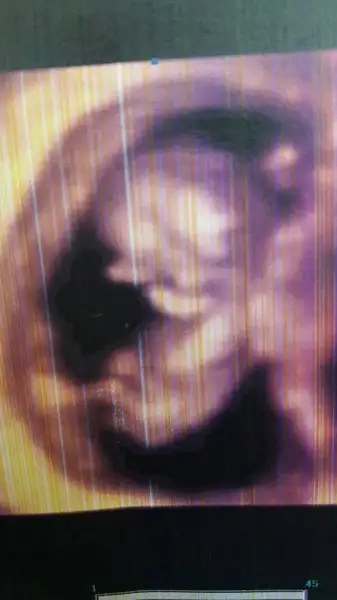

Benim kanamam geçti haftada bir iğne oluyorum cumartesi kontrolüm var bakalım inşallah hepimizin bebişleri iyidirzaten sebebi olmamak icin islerimi aza indirmeye calisiyorum. kendimi yormuamamya calisiyorum. dedigin gibi o benim bebegim ve elimden geleni yapacagim sen simdi nasilsn